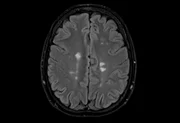

Um novo estudo publicado na revista na última quarta-feira (15/10) revelou uma das razões pelas quais o cérebro das mulheres é mais suscetível a doenças neurodegenerativas, como

Os pesquisadores identificaram que o gene Kdm6a, localizado no cromossomo X, exerce um papel essencial na proteção do sistema nervoso central — e que sua ausência ou mau funcionamento pode deixar as

Segundo os autores, quando o gene é desativado ou alterado, o efeito protetor desaparece, levando a um desequilíbrio na função das microglias, células responsáveis por defender o cérebro de infecções e inflamações. Essa falha de regulação pode contribuir para o surgimento e a

Nos experimentos com camundongos, e danos neuronais semelhantes aos observados em pacientes humanos. As fêmeas apresentaram reações inflamatórias mais severas, confirmando que o efeito do gene está ligado ao sexo biológico e à

O estudo ajuda a explicar de desenvolver esclerose múltipla e são mais afetadas por Alzheimer, especialmente após a menopausa.